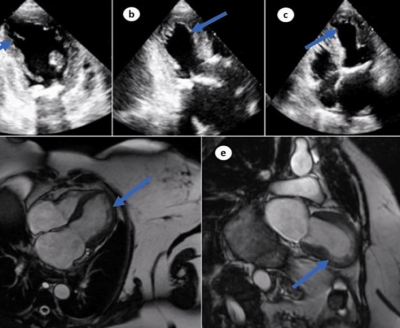

EU-SEARCH NOVICE | Srce po cepljenju napihnjeno kot balon: zdravila za gensko terapijo povzročajo redko obliko kardiomiopatije ...

Srce po cepljenju napihnjeno kot balon: zdravila za gensko terapijo povzročajo redko obliko kardiomiopatije (18.08.2023) | newsexchange ... Težave s srcem, ki jih lahko povzročijo eksperimentalna zdravila za gensko zdravljenje Covid, niso omejene na vnetje srčne mišice. Nedavna študija opisuje primer 59-letnega bolnika, ki je po cepljenju ... | Podobno